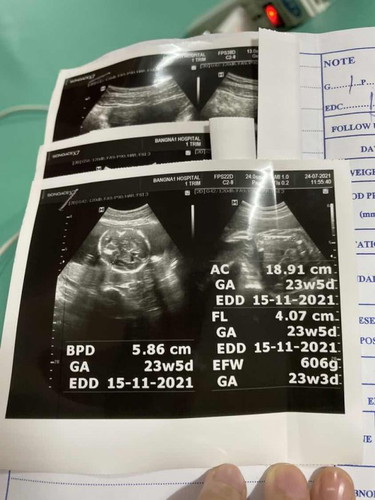

สอบถามแม่ๆหน่อยค่ะ ครรภ์ 23 วีค ลูกโตแค่นี้ ผิดปกติไหมคะ กังวลกลัวเขาโตไม่ตามเกณฑ์ หรือควรกินอะไรบำรุงดีคะ

เพิ่งไปอัลต้าซาวด์มาค่ะ คุณหมอก็ไม่ได้บอกอะไรเลย